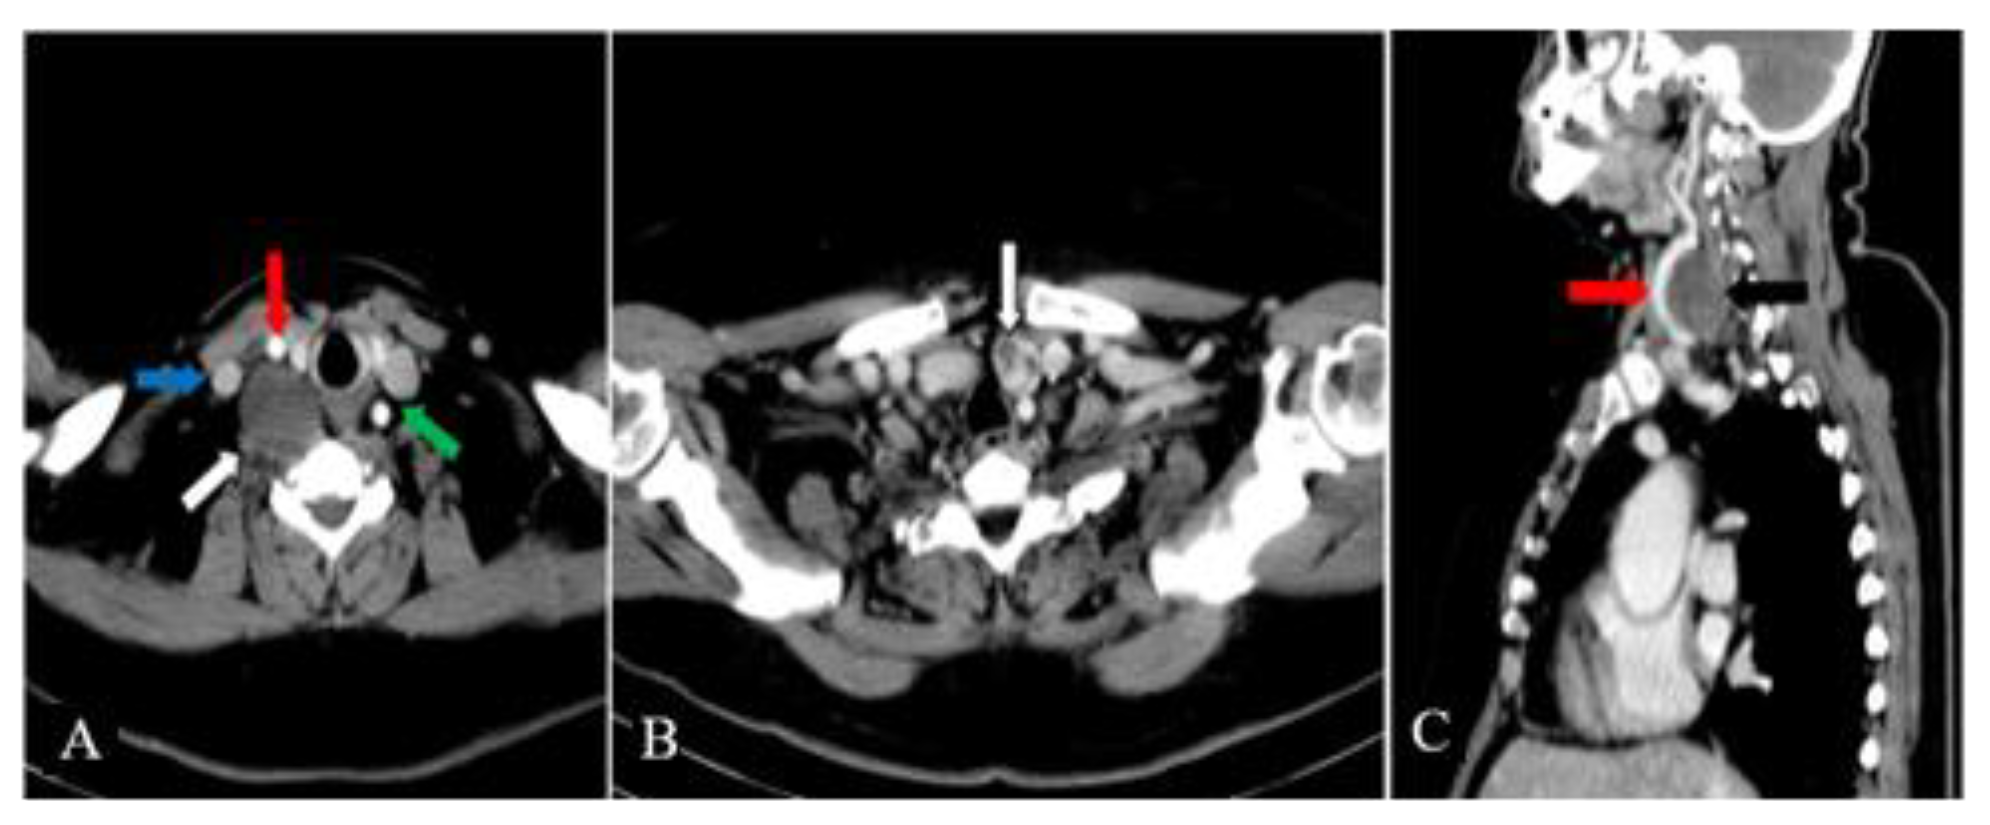

The cervical ultrasound confirmed the presence of a 20/16 mm inhomogeneous nodule within the left thyroid lobe with anechoic areas inside and peripheral blood vessels on color Doppler ultrasound. We did not detect nodules within the isthmus and right thyroid lobe. The 41/31/27 mm right cervical mass was located posteriorly and below the right thyroid lobe, being distinct from it. It pushed forward the right CCA and IJV, splaying them (Figure 1A). The mass was inhomogeneous and showed central and peripheral blood vessels on color Doppler ultrasound (Figure 1B,C). A hypoechoic linear structure seemed to be incorporated into the tumor in an eccentric fashion (Figure 1D).

Figure 1. A. Cervical ultrasound – the right cervical mass (white arrow) is splaying the IJV (blue arrow) and CCA (red arrow) B. Cervical ultrasound - an inhomogeneous appearance of the right cervical tumor C. Color Doppler cervical ultrasound – central and peripheral blood vessels within the right cervical tumor D. Cervical ultrasound – a hypoechoic linear structure (white arrow) is entering into the deep aspect of the right cervical mass in an eccentric fashion.